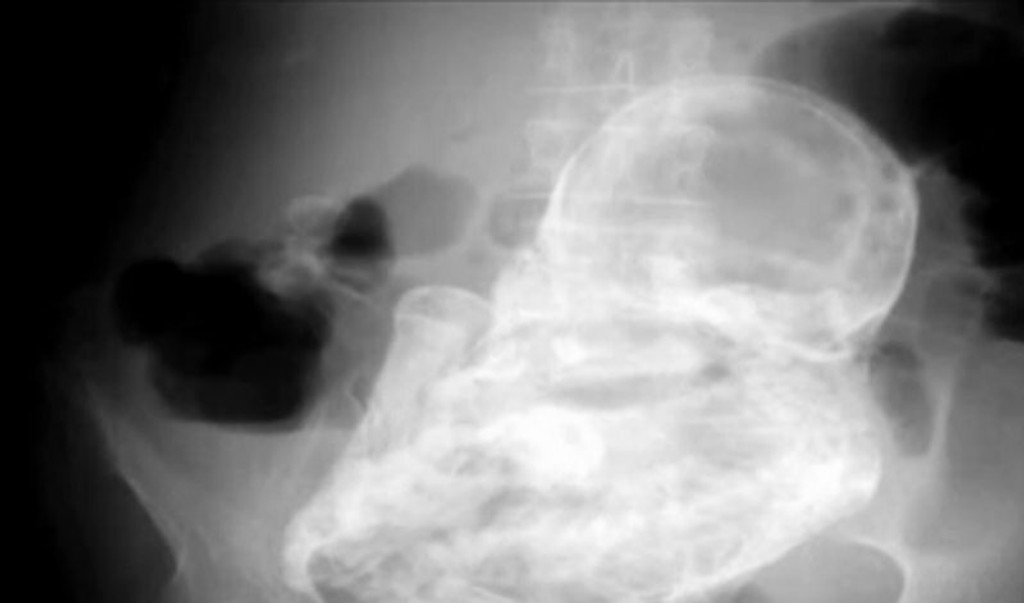

S naozaj nezvyčajným prípadom sa stretli lekári v kolumbijskej nemocnici v Bogote. Na pohotovosť prišla 82-ročná dôchodkyňa s bolesťami brucha. Odborníci si najskôr mysleli, že sú to žlčové kamene, ale skutočná príčina bolesti ich šokovala.

Lekár, ktorý ženu vyšetroval, si všimol v jej brušnej dutine niečo neobvyklé. Pacientke urobili ultrazvuk, ktorý ale nič neodhalil.

Röntgenové vyšetrenie ukázalo pravého vinníka. Lekári sa ale domnievali, že ide o nádor. Neskôr zistili, že to bol kalcifikovaný plod dieťaťa.

Takýto jav nastane vtedy, keď v tele ženy zahynie plod dieťaťa počas mimomaternicového tehotenstva. Označuje sa ako lithopedion alebo „skamenené dieťa".

Plod sa v tele dôchodkyňa nachádzal 40 rokov. Pacientku museli previesť do inej nemocnice, kde podstúpi operáciu, pri ktorej jej plod z tela odstránia.